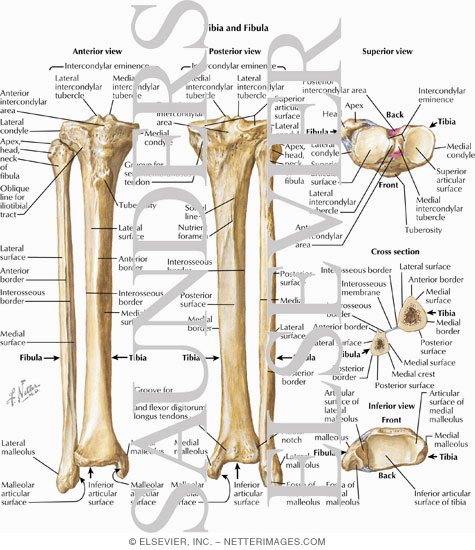

Tibia and Fibula Osteology of the Leg and Knee